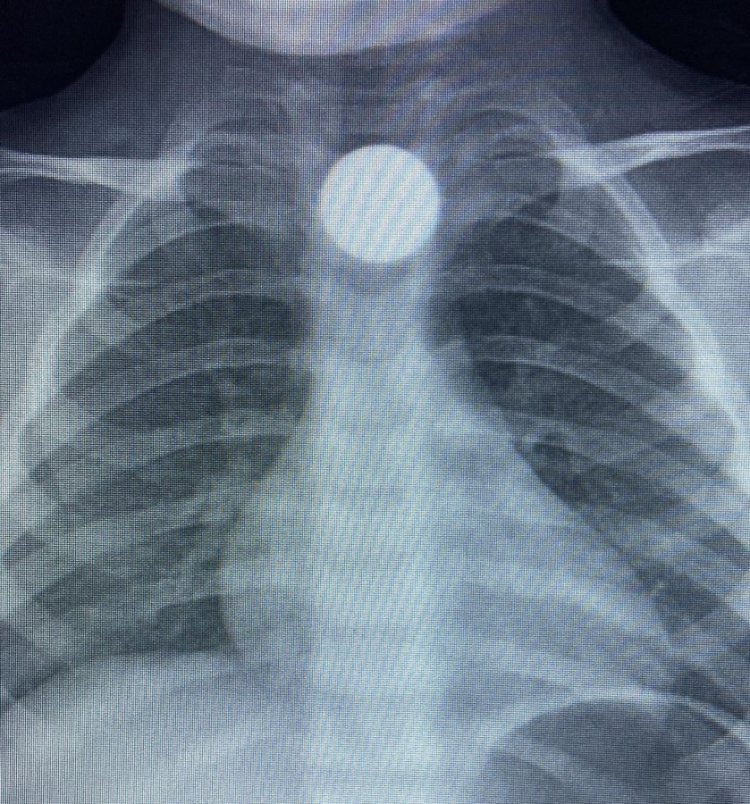

Olay, İnegöl'ün kırsal Yeniceköy Mahallesi'ndeki bir evde meydana geldi. 3 yaşındaki Bilal K., evde yerde bulduğu 50 kuruş madeni parayı ağzına atıp yuttu. Olayı fark eden ailesi tarafından çocuk özel araçla İnegöl Devlet Hastanesi'ne kaldırıldı. Yapılan tetkiklerde yemek borusunda takılı kalan madeni para görüldü. Çocuk ilk tedavinin ardından ambulansla Bursa Yüksek İhtisas Eğitim Ve Araştırma Hastanesi'ne sevk edildi.